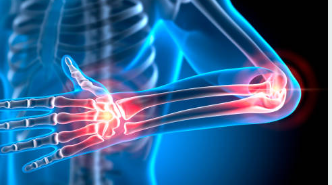

류마티스 관절염은 뼈와 관절, 근육, 힘줄 등을 연결하는 연조직의 염증으로 인해 발생하는 질환입니다. 나이가 들수록 발생 확률이 높아지며, 여성이 남성보다 발생률이 높은 편입니다. 이번 글에서는 류마티스 관절염의 증상에 대해 알아보도록 하겠습니다.

류마티스 관절염은 면역 체계의 오작동으로 인해 발생하는 만성 관절염으로, 주로 손, 발, 무릎, 손목 등의 작은 관절에 영향을 미칩니다.